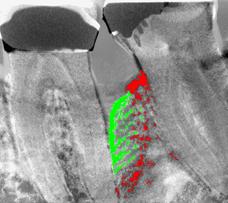

• - Fig. 1 Fig. 2 Fig. 3

• - Fig 3. Digital Subtraction Radiography analysis of the x-rays highlights the regenerated bone in green.